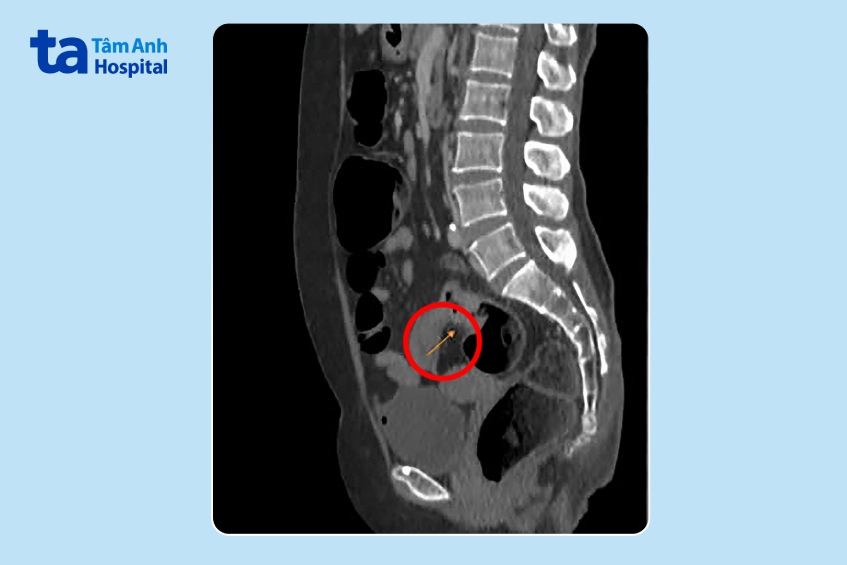

Kết quả nội soi trực tràng của bà Phương tại Bệnh viện Đa khoa Tâm Anh cho thấy u ở lòng trực tràng phát triển gây bán tắc, dạng vòng nhẫn, thâm nhiễm cứng. Kết quả MRI 3 tesla ghi nhận thành ruột dày không đều tại chỗ nối trực tràng với đại tràng sigma (12 mm), trên 30 mm không rõ cấu trúc, tổn thương dạng không nhầy chiếm hết chu vi, gây hẹp lòng đại tràng tại vị trí này.

Trong quá trình phẫu thuật, bác sĩ quan sát chưa thấy nốt di căn, u trực tràng cao co kéo thanh mạc, u to khoảng 5 cm. Bác sĩ cắt ngang trực tràng dưới khối u 4 cm, tiếp đó đưa phần trên đại tràng cùng khối u ra ngoài qua đường mổ nhỏ dưới rốn, cắt ngang đại tràng cách bờ trên khối u 15 cm. Đoạn trực tràng lấy ra dài 25 cm. Sau khi kiểm tra với thuốc nhuộm huỳnh quang ICG cho thấy máu nuôi tốt, bác sĩ tiến hành nối đại tràng với trực tràng bằng máy.